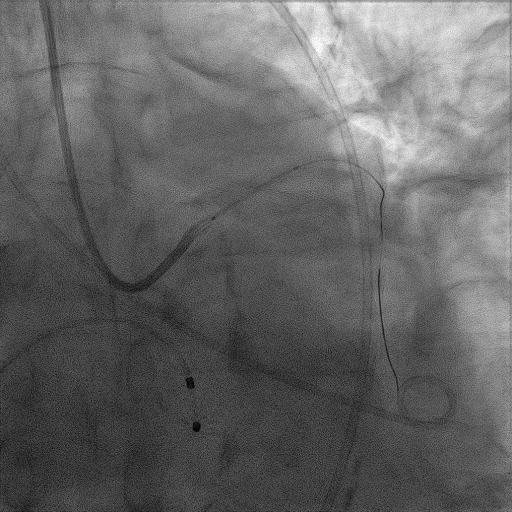

CAG:LAD近中段弥漫钙化,近段80%狭窄,中段90%狭窄,D190%狭窄,中间支近段90%狭窄,右冠近中段弥漫病变,最重狭窄50%。考虑患者胸痛症状可能为冠心病+AS共同作用,以及患者冠脉病变钙化严重,予以旋磨+PCI+TAVR一站式处理。

于中间支植入2.5*18mm支架

1.5mm旋磨头以16万RPM旋磨三次

3.0*15mm球囊后扩张

3.0*15mm球囊预处理LAD近段病变

复查冠脉造影结果满意

造影提示微少量返流,压力监测提示主动脉瓣压差7mmHg